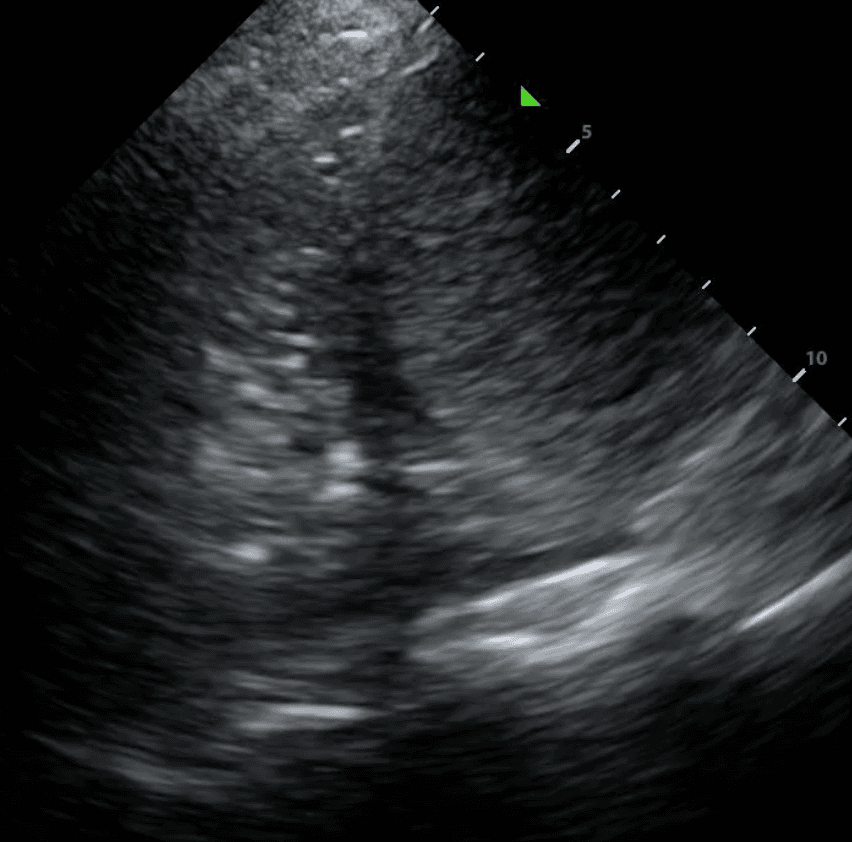

If a pleural effusion is present, there will be an anechoic (ie. black) space above the diaphragm. Please note that an anechoic space below the diaphragm represents ascites; not a pleural effusion. Two other other features will stand out to you. Firstly, you will see a “spine sign.” Normally, the spine cannot be visualized above the diaphragm since aerated lung scatters ultrasound beams before it can reach the spine. However, a pleural effusion will allow sound waves to be transmitted to the spine and you will see the spine clearly visible above the diaphragm.

Secondly, you will see a consolidated lung sitting in the effusion. Please refer to our post on consolidations to learn what consolidated lung looks like. If the effusion is large, the consolidated lung will appear to float in the effusion - resembling a jellyfish swimming in the ocean. This is referred to as the “jellyfish sign.”